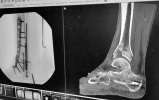

Welp, last month I had one small spot on a gutter screen that had some debris causing some run-over and puddled on my deck. I knew it was gonna freeze and create a hazardous ice sheet. So I got out the ladder and needed to only get up high enough to reach my arm up to the 8' high gutter. I needed to go up one more rung on the ladder to get a better reach and the ladder kick back and out from under me. I came down on my bad ankle from about 6 feet and also rolled back and smacked my head hard on the deck. I knew instantly that my ankle was toast.

Turns out I really did a job on it. When I asked the surgeon if I could lose my foot he didn't exactly say "No". Reading between the lines makes me think that I came close and I am still not out of the woods (so to speak). He stressed many times how serious my injury is, one of the worst he's seen.

Spent a few weeks in the trauma unit with one of those external fixation cages until the swelling went down enough to operate. Left the hospital in a cast and now I'm in a boot...non weight bearing for at least another couple months. Walker and crutches and a knee scooter on the way.

I now have a fuzed ankle, and in me I have more hardware than a piece of modern archery gear.

View attachment 125486